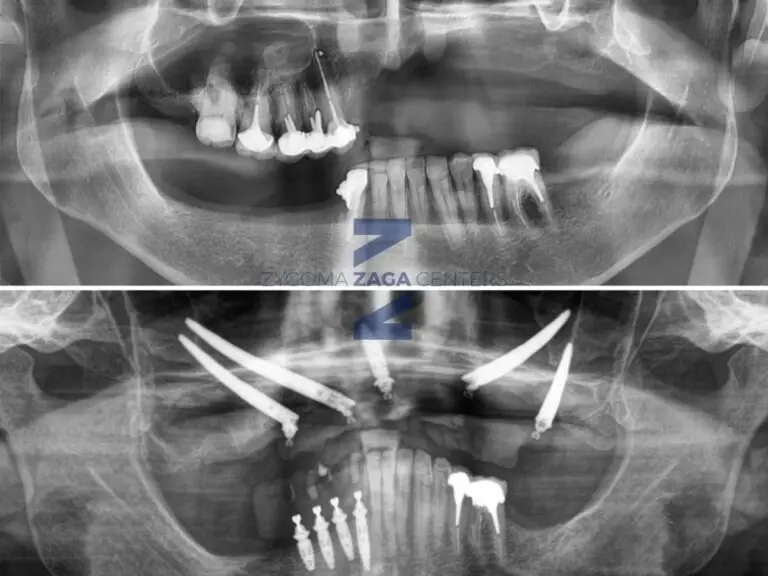

Zygomatic Implants in a Case of Severe Atrophy: ZAGA Center Paris

Full-Arch Fixed Rehabilitation with Zygomatic Implants in a Case of Severe Atrophy: A Case Report by ZAGA Center Paris Case realized by Dr. Umberto Russo, member of the ZAGA Centers network 1. Clinical Context and Treatment Limitations The clinical course of this 46-year-old patient began with a major facial trauma